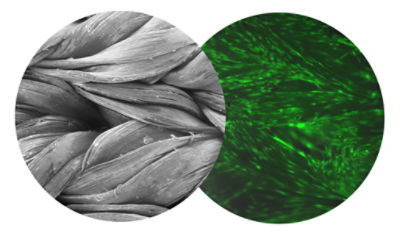

Artelon doesn’t just support the repair. It integrates with the body. Our permeable, synthetic scaffold is designed to integrate with the body’s connective tissue over 4 –6 years1,2,6, encouraging natural tissue in growth and load sharing which may support regenerative biological signaling.7,8 This load-sharing design helps the body support stronger tissue with long term bio-integration.

SEM images of FlexBand Matrix and hTenocytes proliferation at 8 days10 (shown in neon green).